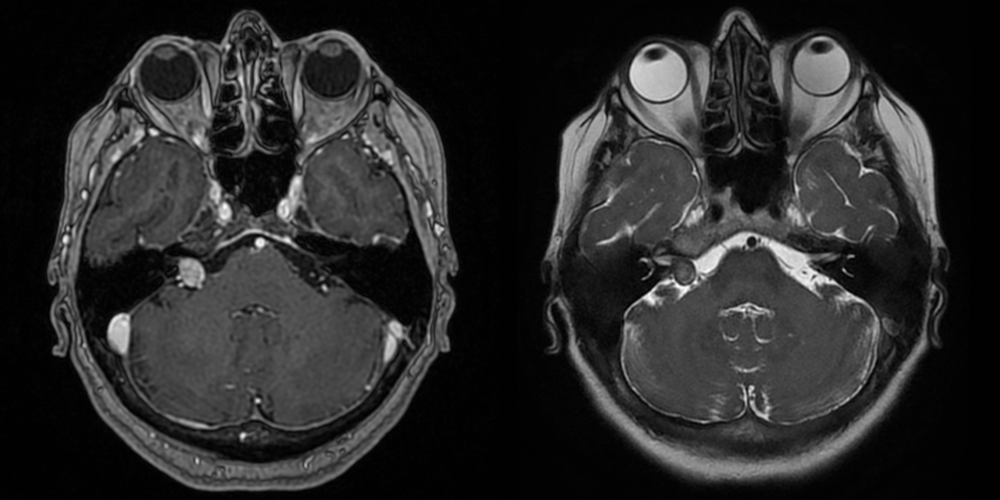

Meningiom olfactiv – RMN preoperator

Meningiom olfactiv – RMN postoperator